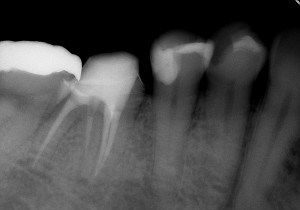

↑根の治療終了後

その後は、歯の土台を作りしっかり補強した後、仮歯を入れて咬んでも痛くないか、歯肉の腫れは再発しないかなど経過観察をしました。